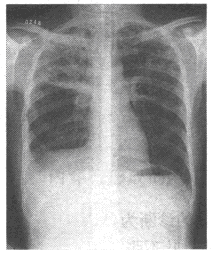

47、单项选择题

患者,男,3岁,突发左侧胸痛伴呼吸困难3小时入院,如图所示,最可能的诊断为()

A.左侧肺气肿

B.左侧气胸

C.左肺门淋巴结结核

D.右肺小叶性肺炎

E.以上都不正确

点击查看答案